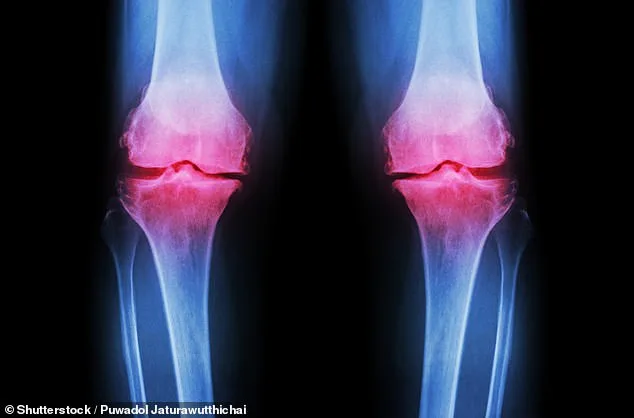

Osteoarthritis affects over 10 million people nationwide, with symptoms ranging from persistent joint pain to severe stiffness that limits daily activities. Current treatments often rely on painkillers or physiotherapy, both of which come with limitations. Medications can lead to gastrointestinal issues or dependency, while physiotherapy demands consistency and access to resources many struggle to maintain. Now, this study raises a compelling question: what if the answer to managing osteoarthritis lies not in pharmaceuticals but in something as simple as a spoonful of fibre?

The research followed 117 adults with knee osteoarthritis participating in the INSPIRE trial. They were randomly assigned to receive either inulin, physiotherapy, a combination of both, or a placebo. The results were striking: participants taking inulin alone experienced measurable reductions in pain sensitivity and improvements in grip strength—metrics that have long been linked to overall physical health. One participant, a 68-year-old woman who had struggled with daily tasks for years, reported being able to walk without a cane after six weeks of taking the supplement. Could this be the first step toward a more holistic approach to arthritis care?